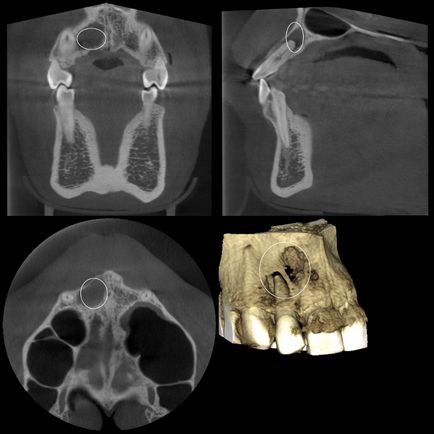

Cyst felső állkapocs (konzervatív kezelés)

Az eredmény 4 hónap után a kezelés